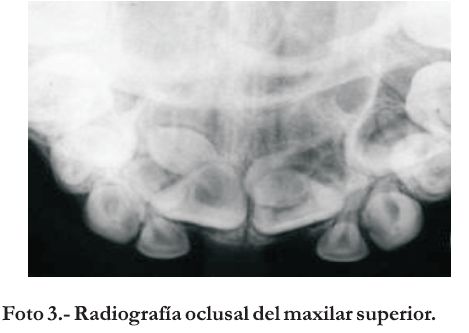

En el examen radiográfico se observaron dos elementos supernumerarios proyectados uno a nivel del tercio apical de 11/12 mostrando un grado avanzado de formación y en posición invertida y el otro proyectado sobre el germen dentario del 21. Ambos dientes supernumerarios pueden observarse en una toma oclusal (Foto 3) realizada en una consulta posterior.

Fueron realizados controles clínicos, radiográficos y ortodóncicos del caso durante la fase de expansión maxilar y remodelación de la sutura palatina. Después de tres meses se observa a través de una radiografía oclusal el comienzo de la osificación de la sutura palatina media (Foto 3). En este período de tres meses sucede una reorganización sutural del maxilar y una dispersión de las fuerzas residuales acumuladas (15-17). El aparato expansor fue removido cinco meses después de su colocación.